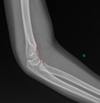

1

Not at all

2

3

4

5

Perfectly